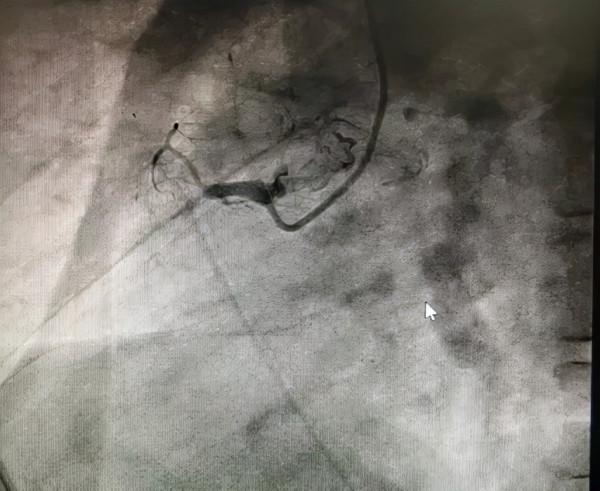

成功透過血管內膜下重新進入遠端血管真腔,經過多體位投照、逆向造影均證實為真腔,順利開通閉塞病變。

正向造影可見右冠全程瀰漫狹窄病變

序貫植入4枚第二代藥物洗脫支架覆蓋病變。

無術中併發症,手術完美收官。